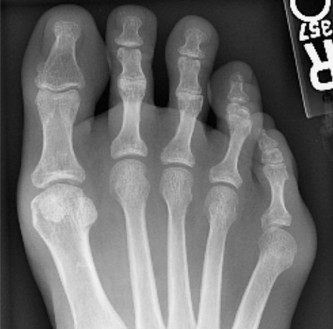

Question 29

Which of the following best describes a Jones fracture? tarsometatarsal joint. the fourth–fifth intermetatarsal articulation. fourth–fifth intermetatarsal articulation. fifth intermetatarsal articulation.

Explanation:

Fracture at the metaphyseal–diaphyseal junction of the fifth metatarsal at the level of the fourth–fifth intermetatarsal articulation. Fractures of the base of the fifth metatarsal are common. They are classified into zones according to location: Zone 1 – Proximal metaphyseal fracture of the fifth metatarsal at the level of the tarsometatarsal joint Zone 2 – Fracture at the metaphyseal–diaphyseal junction of the fifth metatarsal at the level of the fourth–fifth intermetatarsal articulation Zone 3 – Fracture at the proximal diaphysis of the fifth metatarsal distal to the level of the fourth–fifth intermetatarsal articulation The zone 2 injury is also known as a Jones fracture, after Sir Robert Jones. 216